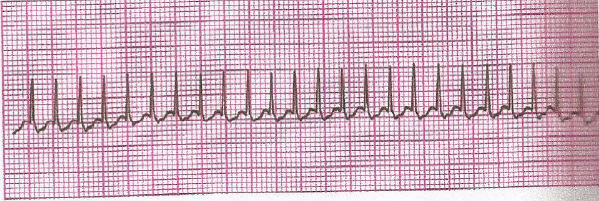

Lactente com miocardiopatia apresenta abruptamente irritabilidade, com período de sonolência, palidez cutânea, taquipneia com aumento do esforço respiratório, estertoração em bases pulmonares, FC = 260 bat/min, PAS = 60 mmHg, pulsos periféricos fracos e extremidades frias. É transferido para UTI com oxigênio e com dificuldade de acesso venoso disponível. Baseado na clínica e no ECG abaixo, assinale o diagnóstico dessa situação e a medida a ser adotada: